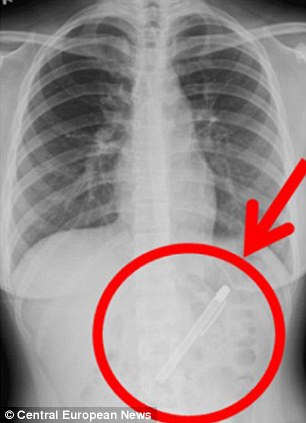

Բժիշկները էնդոսկոպիայի միջոցով նրա ստամոքսում երկարավուն առարկա են նկատել, որից հետո ռենտգենյան ճառագայթներով հետազոտության արդյունքում պարզվել է, որ աղջկա ստամոքսում կես տարի շարունակ գրիչ է եղել:

Բժիշկները անմիջապես վիրահատել և հեռացրել են գրիչը: